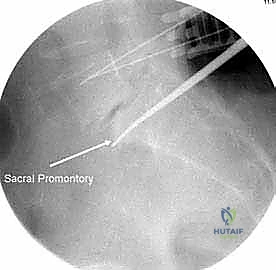

3. السويقات العجزية (S1):

* الحجم: سويقة الفقرة العجزية الأولى (S1) هي الأوسع والأضخم بين جميع السويقات، مما يوفر نقطة تثبيت قوية جداً لقاعدة البناء الجراحي.

* المخاطر: التوجيه الدقيق مطلوب لتجنب اختراق المفصل العجزي الحرقفي أو إصابة الأعصاب العجزية.